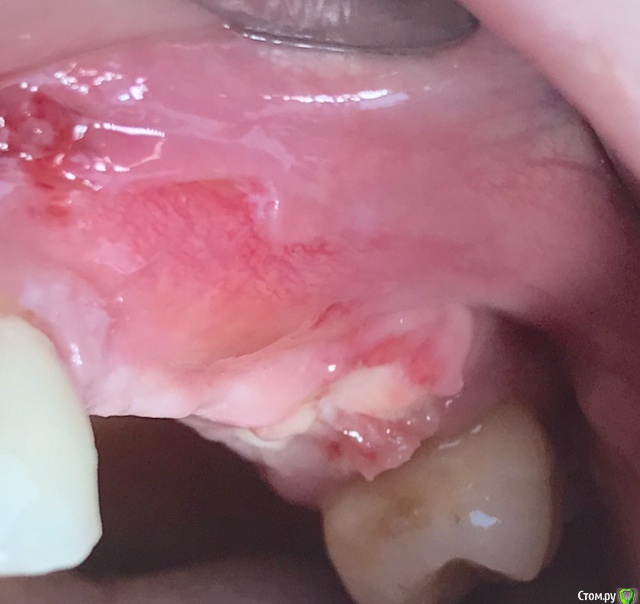

колесников Опубликовано 15 марта, 2019 Автор Поделиться Опубликовано 15 марта, 2019 Вот так выглядит интегрированый графт и соответственно не созревший. Время ожидания примерно равнозначное Ссылка на комментарий

колесников Опубликовано 16 марта, 2019 Автор Поделиться Опубликовано 16 марта, 2019 (изменено) Ну как бы тут все очевидно. Слева стала костью,справа нет. Но должен вам отметить,что даже в случае неудачи (как кажется)потери нет. Задача стояла не увеличить объём для имплантации или укрыть Имплант,а снять напряжение с вершины гребня и дать созреть десне. Имплант в нативной кости,он интегрирован,десна успела созреть за это время,возможно будет не так объёмно как хотелось бы,но у меня в запасе этап раскрытия ,фдм зарос ,есть с чем поработать. Все что не интегрировалось ,лизируется самостоятельно,выскребать ничего не нужно,ещё подождать. Изменено 16 марта, 2019 пользователем колесников Ссылка на комментарий